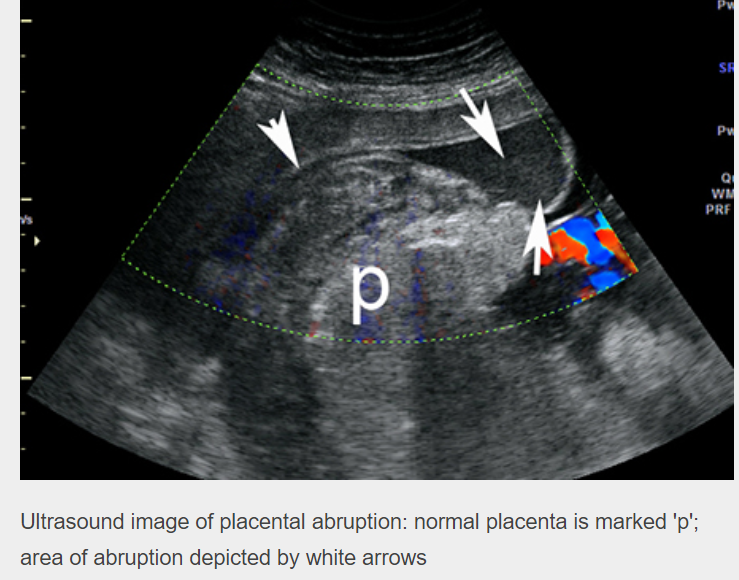

US findings in placental abruption:

Findings may include: